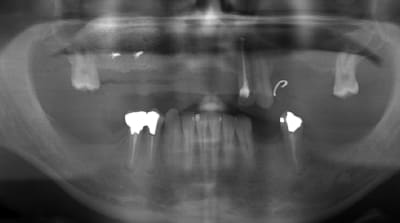

là, la 53 est en train de flancher (et j'ai pas la place pour 2 implants, donc compromis esthétique...), elle sais qu'elle va se retrouver avec un bon gros trou devant...elle a réfléchit, elle est prête...reste juste à voir si le devis "passe" parce qu'avec une double greffe, même si je suis pas très cher, çà commence à faire une somme rondelette...

Implant 13 et couronne 13-X

Evite 2 implants de suite en zone esthétique.

Exo 53 et un implant dans ce site avec pontique 12.

diamètre 3.7mm pour les 2 implants

je vérifierai lundi (j'ai pas l'analyse à la maison) mais il me semble que le site de la 53 est encore pire que pour la 12...

j'avais au départ imaginé poser 2 mini implants, mais j'ai vite abandonné cette option...et c'est un cas pas simple à gérer esthétiquement...